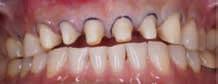

The patient initially reported the CC of “My teeth are breaking”. Upon assessment, notable findings included erosion of the lingual surfaces of anterior teeth and fractured incisal edges. Diagnostic casts were made, and a comprehensive digital smile design was completed. Subsequently, a 3D printed model was generated and a PVS matrix was fashioned to create a mock-up, providing the patient with a visual representation of the proposed treatment plan. Recognizing the need to increase the clinical crown, crown lengthening was determined necessary. Following this procedure, crown preparations were completed. Provisional restorations were fabricated based on mock-up template, allowing the patient to preview the anticipated outcome. After ensuring optimal occlusion through final adjustments, the patient was scanned with the temporaries in place. This scan was then forwarded to the dental laboratory for the fabrication of the definitive restorations.

Left: Figure A. Pre-op, Figure B. Chairside mock-up, Figure C. Crown lengthening procedure. Right: Figure D. Crown preparations, Figure E. Provisional restorations, Figure F. Final restorations.